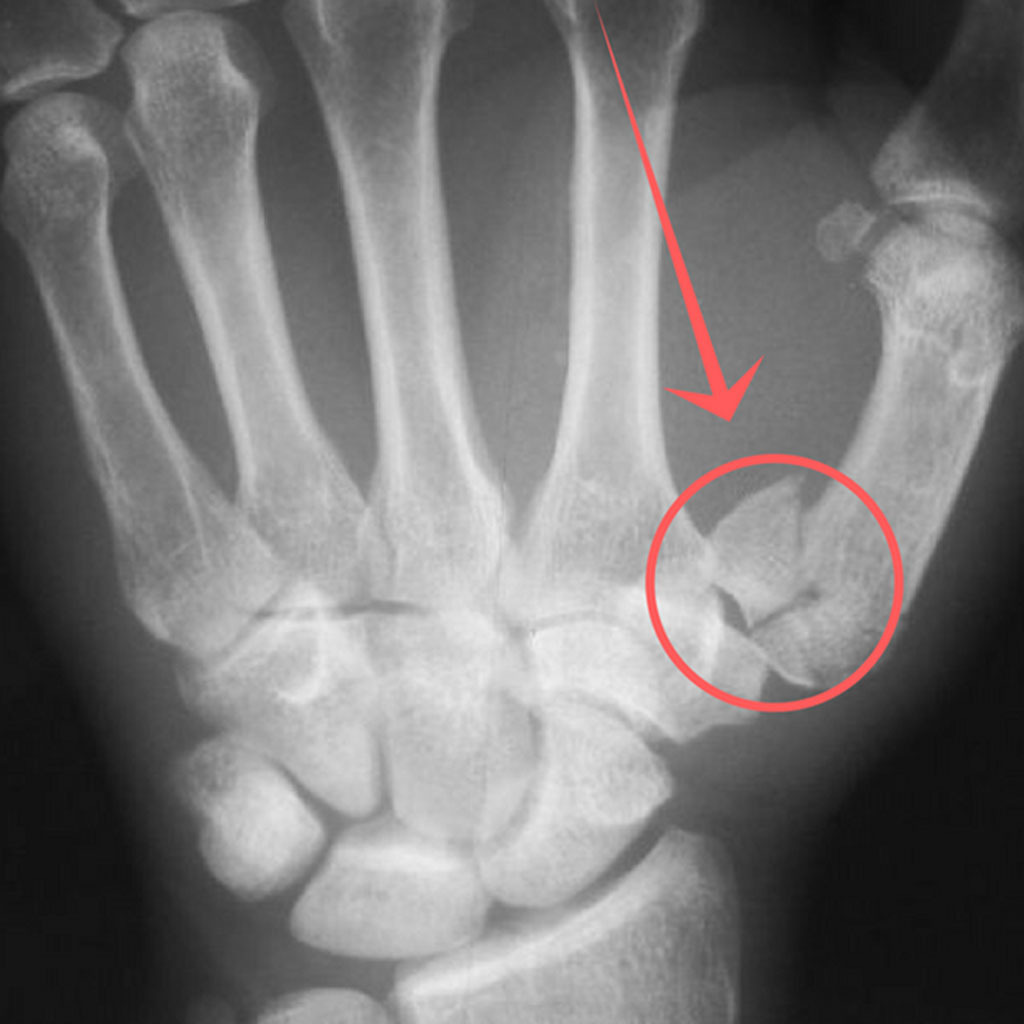

손가락 골절은 기저부(base) 골절, 중간부(shaft) 골절, 관절면(intra-articular) 골절 등으로 나뉘며, 특히 관절면을 침범한 골절은 기능적 후유증이 남을 위험이 높습니다. 따라서 엑스레이 검사로 정확한 위치와 손상 정도를 파악하고, 필요 시 CT나 초음파로 인대 손상 여부를 함께 확인해야 합니다.

손가락에 금이 갔을 때 중요한 것은 정확한 진단입니다. 단순히 통증이 있다고 해서 자가진단으로 테이핑만 하는 것은 위험하며, 반드시 엑스레이 검사를 통해 뼈의 정렬 상태와 골절선을 확인해야 합니다.